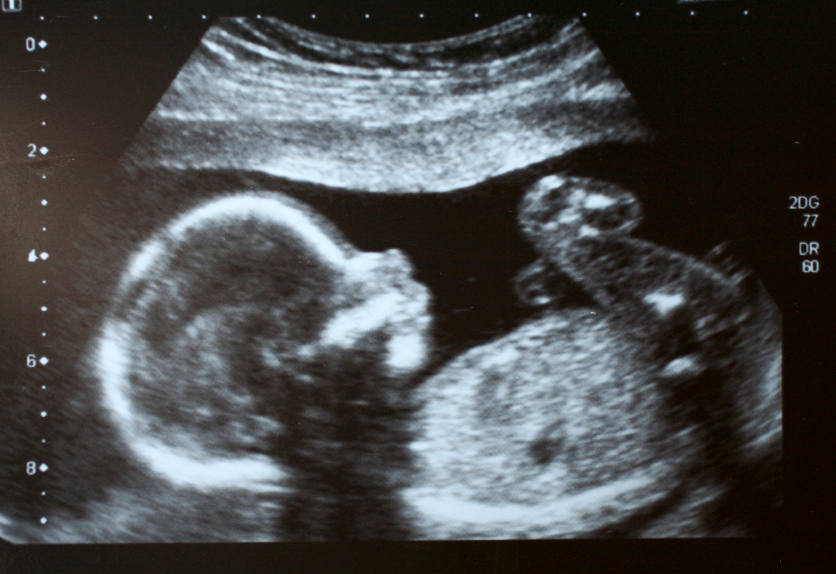

Kombinovani skrining je pretraga kojom se procjenjuje rizik za nastanak hromozmskih bolesti ploda. Obavlja se u periodu između 11. nejdelje i 13. njedlje i 6 dana trudnoće. Stastoji se od transvaginalnog ultrazvučnog pregleda i biohemijske anlize majčine krvi.

Kombinovani skrining je savremeni neinvazivni pristup u prenatalnoj dijagnostici ploda. On je kombinacija biohemijskih i ultrazvučnih markera. Od biohemijskih markera upotrebljava se: βHCG i PAPPA. Kao ultrazvučni marker koristi se doktrinarno izračunata vrijednost veličine nuhalnog nabora, detekcija nosne kosti, dužina fetusa (CRL) i širina glavice ploda (BPD). Uzima se također i podrobna anamneza trudnice, tačni podaci o dobi i prvom danu zadnjeg menzesa. Podaci se pohranjuju u poseban certificirani kompjuterski program „PRISCA“ koji izračunava rizik da plod ima genetsko oboljenje. Ova metoda ima visoku pouzdanost od svih pobrojanih metoda skrininga na genetsku bolest fetusa.